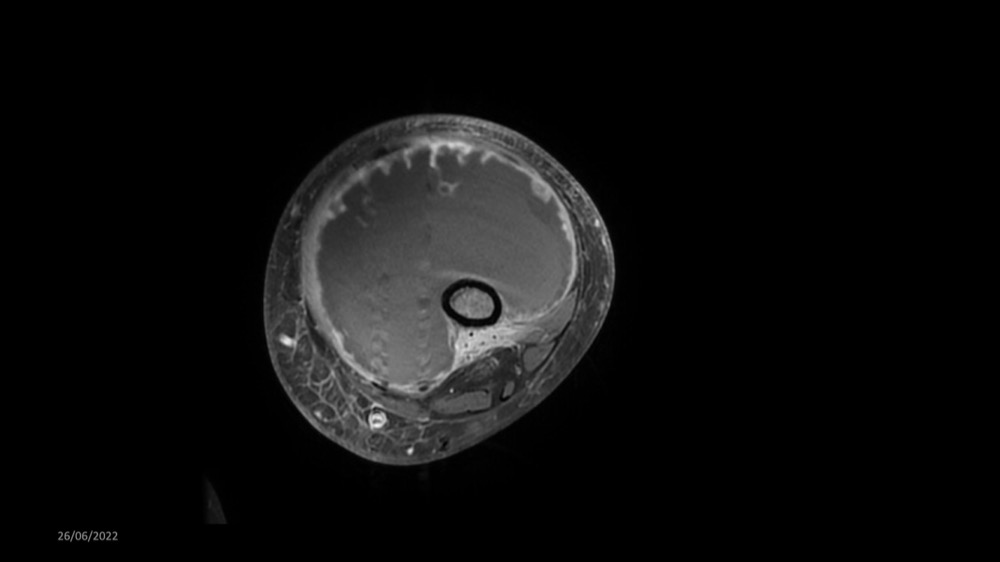

Reichert / Amar / Tordjman / Carlier 29/06/2022